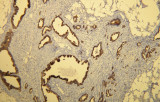

Studi recenti sottolineano il valore diagnostico delle proteine del complesso SWI/SNF, in particolare ARID1B, nell’identificazione di malignità ginecologiche dedifferenziate e indifferenziate – tumori aggressivi con prognosi sfavorevole. L’IHC di ARID1B offre alta specificità e viene sempre più integrata nei pannelli diagnostici per migliorare la precisione. Pannelli con marcatori aggiuntivi supportano anche la differenziazione dei sarcomi uterini, aumentando l’accuratezza diagnostica. Evidenze emergenti suggeriscono che ARID1B potrebbe rappresentare un potenziale bersaglio terapeutico nel carcinoma ovarico a cellule chiare, sebbene le applicazioni cliniche rimangano in fase di ricerca.

- Ruolo complementare alla diagnostica molecolare: L’integrazione con sequenziamento e altri dati molecolari migliora la classificazione tumorale completa, come illustrato nella gestione del carcinoma endometriale.